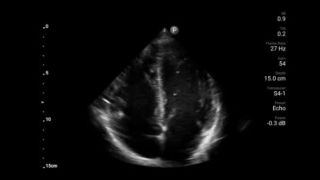

Lumify S4-1 broadband phased array transducer

• 4 to 1 MHz extended operating frequency range • 2D, color Doppler, M-mode, advanced XRES and multivariate harmonic imaging • High-resolution imaging for abdominal and cardiac applications: Cardiac, OB/GYN, Lung, Abdomen and FAST imaging preset optimizations